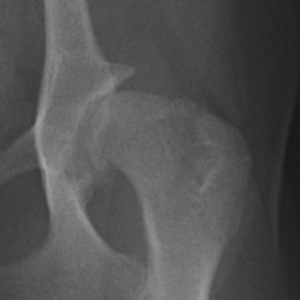

股関節形成不全に起因する関節炎のレントゲン像

①寛骨臼(骨盤側の関節の受け皿)

②大腿骨頭(太ももの骨の関節の頭)

③大腿骨頚(太ももの骨の関節の首)

の重度の変形